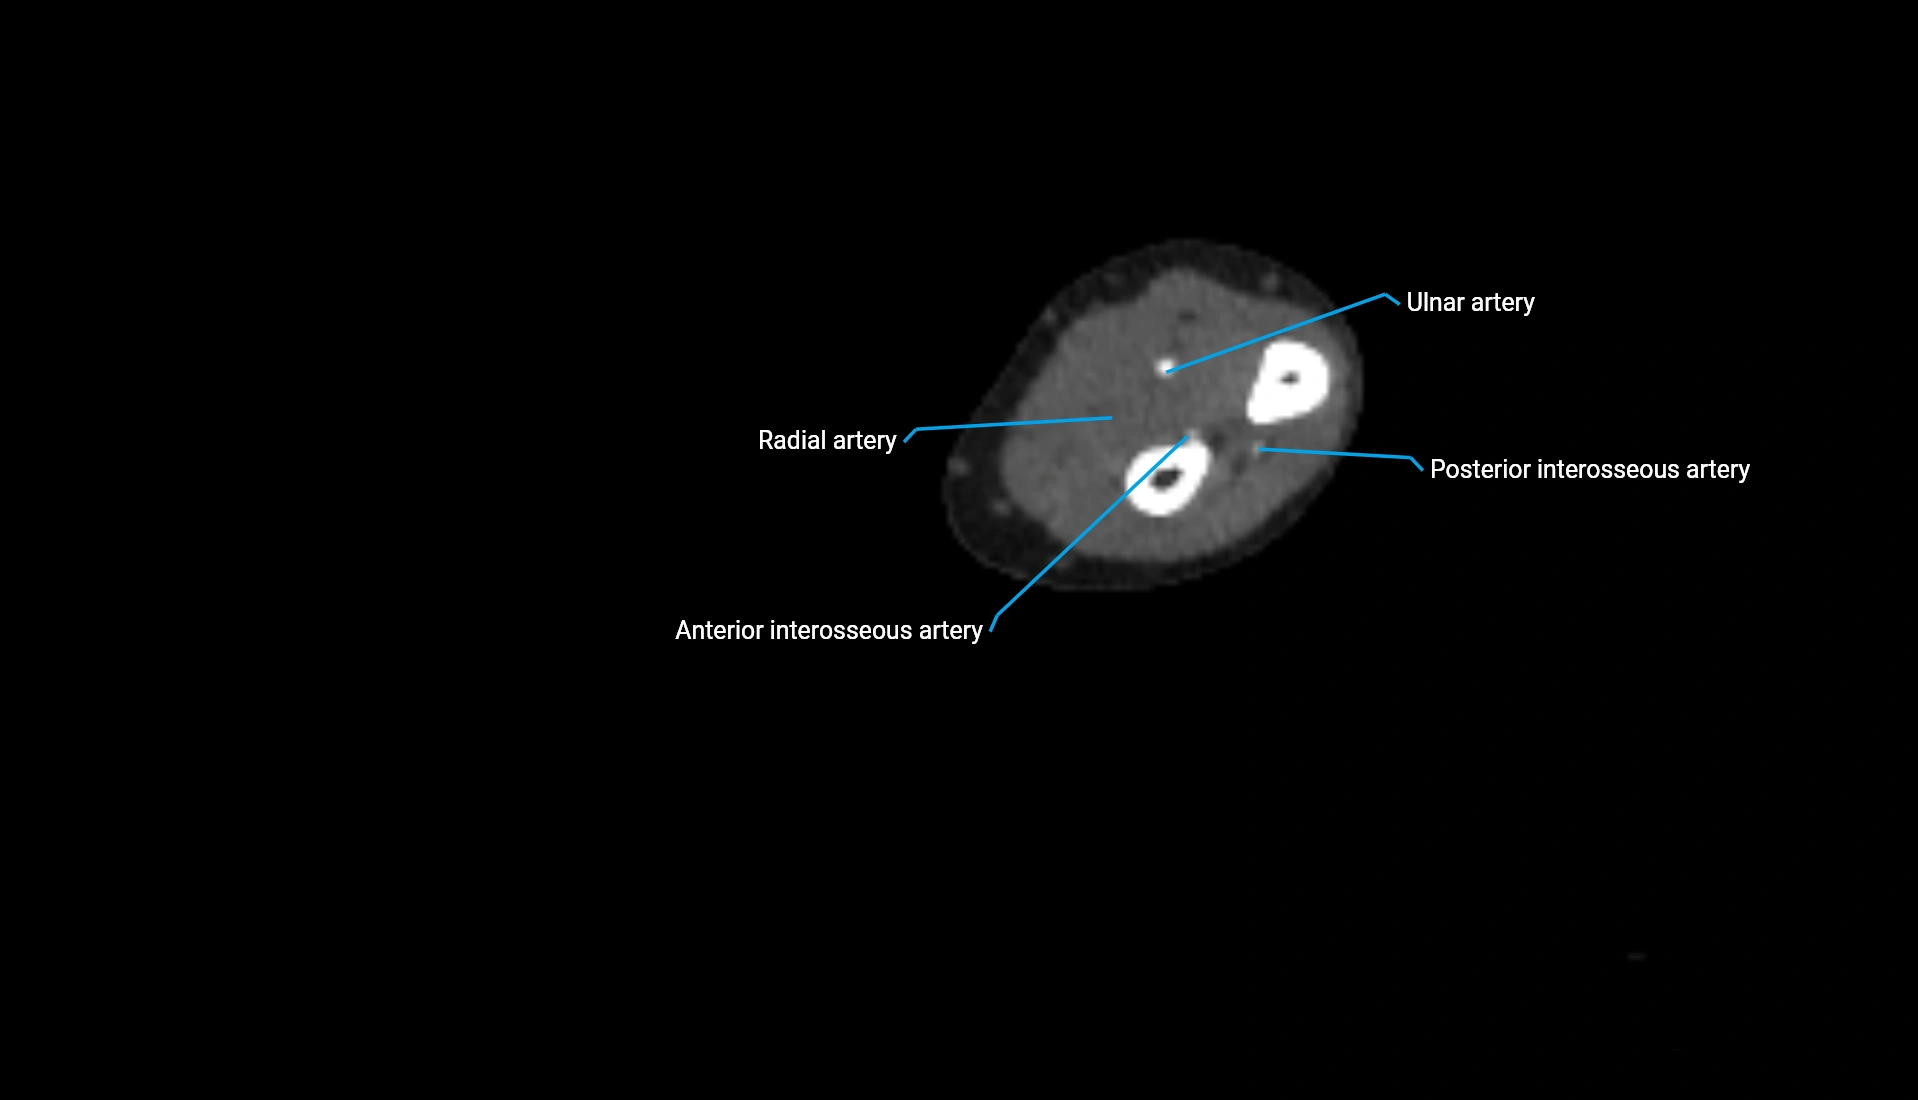

CT Appearance

Non-Contrast CT:

• Cortex: High-density, sharply defined

• Subchondral bone: Dense cancellous matrix

• Articular surface: Smooth concave contour articulating with the capitellum

• Excellent for evaluating bone integrity, alignment, and subtle fractures